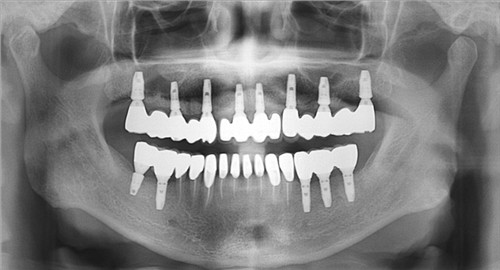

每个人都想有一张美丽的笑容,但是牙齿缺失让很多人很苦恼。口腔种植牙可以帮助我们改变这个情况。现在牙齿修补方法中口腔种植牙是不错的选择。口腔种植牙有什么条件吗?下面是对口腔种植牙的条件的介绍。 ...

牙种植是一种常见的牙齿整形,大家在做牙种植前应简单的了解下牙种植的相关知识,下面就请专家为大家详细的介绍下牙种植体的过程。 ...

种植牙是继传统可摘活动和固定镶牙方法之后出现的一种全新的镶牙技术,它的出现给广大的口腔疾病患者带来了便利,越来越多的患者选择种植牙手术来矫正自己的牙齿问题,那么种植牙具有哪些突出的优点呢? ...

牙齿缺失是比较常见的现象,牙齿缺失会影响美观,但是由于很多人对于种植牙不了解,所以存在很多误区,今天我们的专家介绍一下种植牙的六大误区,爱美的你赶快来听听专家的介绍吧。...